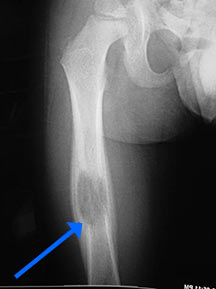

Рисунок 2. Эозинофильная гранулема кости: поражение бедра у девочки 11 лет (рентгенограмма). Отмечались припухлость и боль в течение 3 мес.

https://radiopaedia.org/cases/langerhans-cell-histiocytosis-skeletal-manifestations